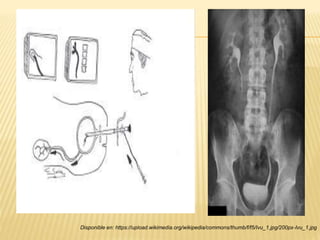

“PIELOGRAFÍA RETROGRADA”

 Procedimiento muy poco invasivo.

 Cistoscopia y placa de abdomen.

 Medio de contraste radiopaco a través de sondas

uretrales.

 Utilización de anestesia (lidocaína al 10%).

 Posterior al estudio:

- IVU

- Reacciones de hipersensibilidad al contraste.

Smith y Tanagho, "Urología general", Ed. Mc Graw Hill, ed. 18a, impreso cd. de México, 2008, pág. 66

Disponible en: https://upload.wikimedia.org/wikipedia/commons/thumb/f/f5/Ivu_1.jpg/200px-Ivu_1.jpg